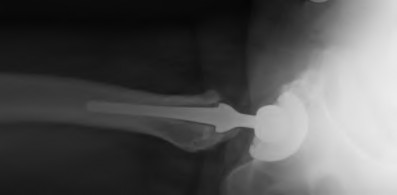

A 35-year-old male presents with right hip pain. MRI confirms avascular necrosis (AVN) of the femoral head. Radiographs show a distinct sclerotic band and cystic changes in the femoral head, but no subchondral collapse or crescent sign. According to the Ficat and Arlet classification, what stage is this, and is core decompression generally indicated?

Explanation